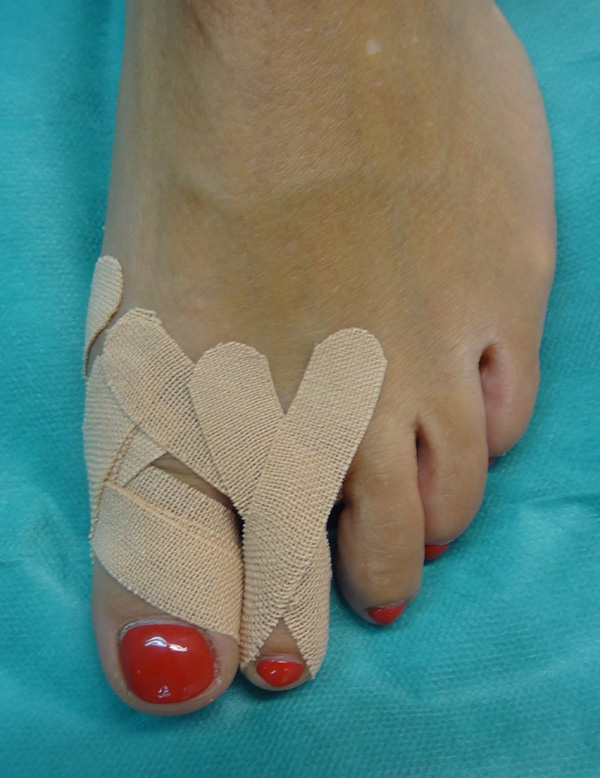

Sämtliche Operationsschritte werden über kleine Stichinzisionen durch die Haut durchgeführt. Isham beschrieb das Verfahren ohne Osteosynthese. Da es sich bei den knöchernen Korrekturen um mediale Closing wedge Osteotomien handelt, werden diese anschließend durch spezielle Zügelverbände (Tape) in Position gehalten. Postoperativ ist eine sofortige Vollbelastung im flachen Verbandsschuh möglich, der Wechsel auf Konfektionsschuhe erfolgt meist nach 4 bis 5 Wochen.

• Notwendigkeit der Anlage von Spezialtapes. Diese sollte nur vom Operateur selbst gewechselt werden, wöchentliche Kontrollen mit Tapewechsel notwendig.

• Verbandmaterial zum Anlegen eines Redressionsverbandes (sterile Kompressen, sterile Watte, Haftbinde, Tape).

• Verbandswechsel (vom Operateur selbst) 7, 14, 21 und 28 Tage postoperativ mit Freigabe nach 4-6 Wochen.

• Korrekturverlust durch falsche Tape-Technik postoperativ.